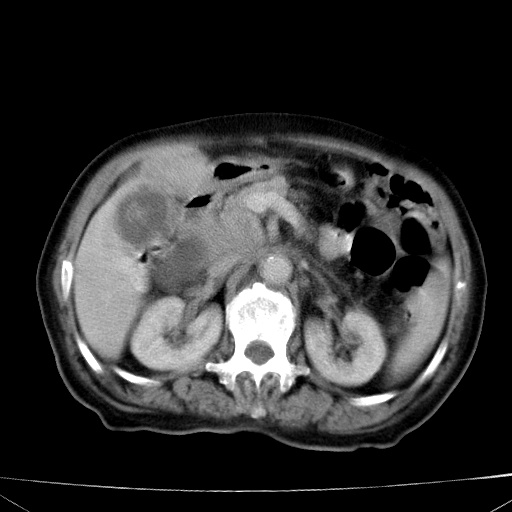

网站人气太旺!昨天的帖子就沉到海底,只好再发贴!ct18338:女 78岁,肝胆病变,已增强,再会诊!原帖链接:http://www.radida.com/bbs/forum.php?mod=viewthread&tid=50032

1)考虑胆囊癌侵犯肝脏并肝门区、腹膜后及右侧膈角后淋巴结转移。2)肝左叶近肝顶部囊肿。3)肝左叶肝内胆管结石。4)左肾近下极囊肿。